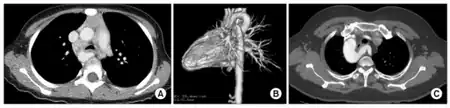

A vascular ring is a congenital defect in which there is an abnormal formation of the aorta and/or its surrounding blood vessels. The trachea and esophagus are completely encircled and sometimes compressed by a "ring" formed by these vessels, which can lead to breathing and digestive difficulties.[1][2]

Infants with vascular rings typically present before 12 months with respiratory or esophageal symptoms like stridor, wheezing, cough, dysphagia, or difficulty feeding. The stridor improves with neck extension, differentiating from laryngomalacia which is relieved by prone or upright positioning, and will not be relieved with corticosteroids or epinephrine, unlike croup. Diagnosis requires a high degree of clinical suspicion and can be confirmed with barium contrast esophagogram for those with esophageal symptoms, bronchoscopy, or CT or MRI.[3]